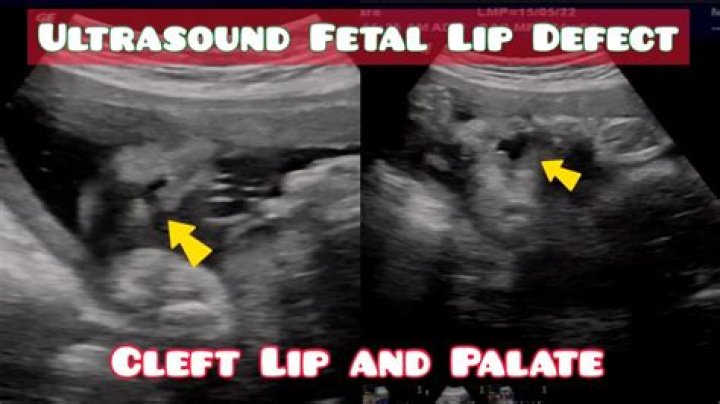

Can a cleft lip be seen on ultrasound?

Cleft lip may be detected with ultrasound beginning around the 13th week of pregnancy. As the fetus continues developing, it may be easier to accurately diagnose a cleft lip. Cleft palate that occurs alone is more difficult to see using ultrasound.

How is a cleft palate detected?

How is cleft lip/cleft palate diagnosed? In most cases, a prenatal ultrasound can detect cleft lip alone or cleft lip and palate as early as 16 weeks into a pregnancy. The diagnosis is then confirmed at birth with a detailed visual assessment and physical examination.